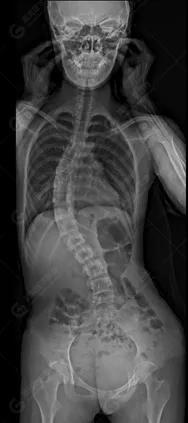

15歲女性,發(fā)現(xiàn)特發(fā)性脊柱側(cè)彎3年,于2019年1月23日來到廣東高尚醫(yī)學(xué)影像診斷中心行EOS檢查,2019年2月行手術(shù)治療后多次到中心行EOS復(fù)查。

2019-01-23

脊柱側(cè)彎最重要一個臨床參數(shù)是側(cè)彎角(Cobb角),目前臨床公認(rèn)的Cobb角>10 °診斷為脊柱側(cè)彎;如Cobb角進(jìn)行性持續(xù)性增加>40 °需要手術(shù)矯正治療。

本例患者胸椎右側(cè)彎,Cobb角(T6/T12)為47°,遂行手術(shù)矯正治療。術(shù)后多次隨訪的Cobb角(T10/L3)為12°-15°之間,較術(shù)前明顯縮小。